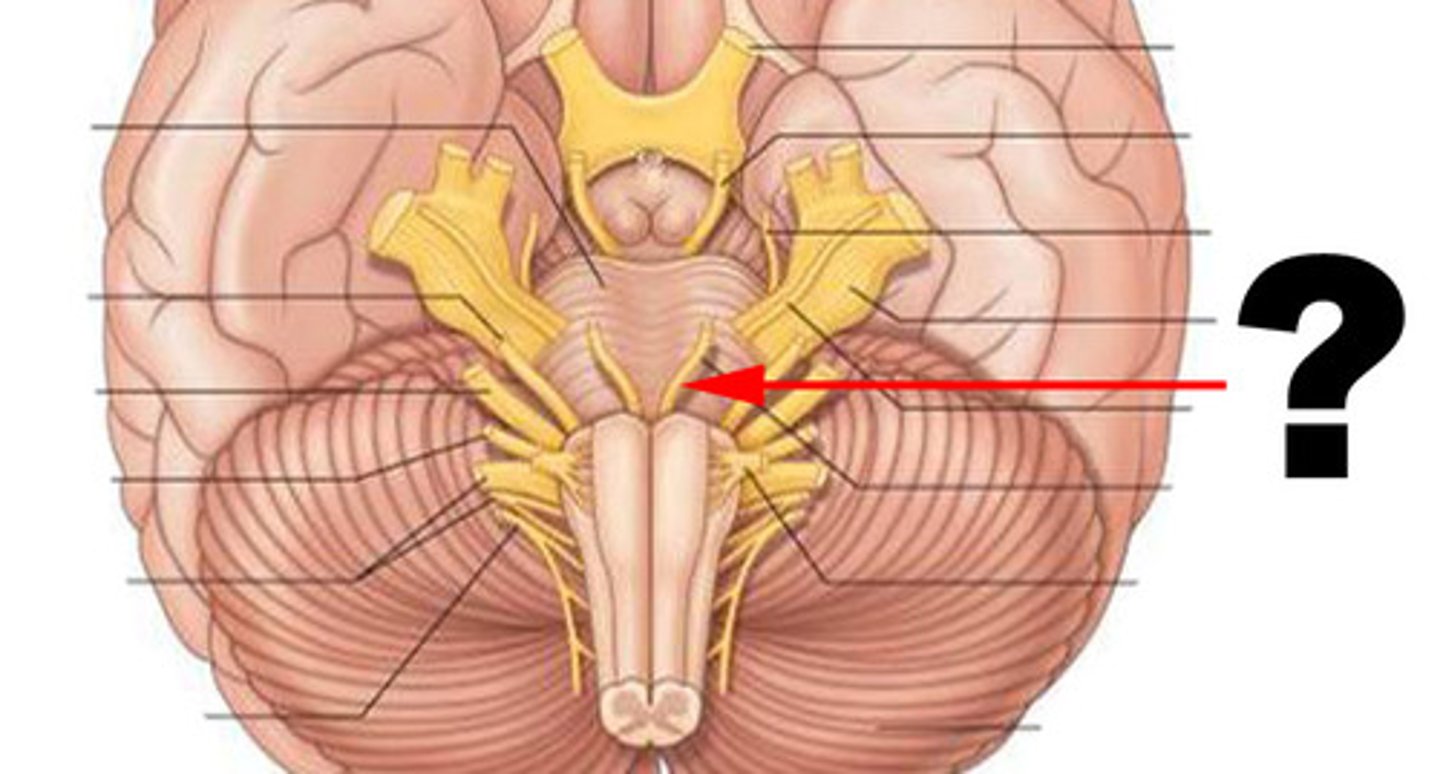

pons

medulla oblongata

pyramids

inferior cerebellar peduncles

CNIV (trochlear nerve)

CNVI (abducens nerve)

CNIII (oculomotor nerve)

CNVIII (vestibulocochlear) (acoustic nerve)

CNX (vagus nerve)